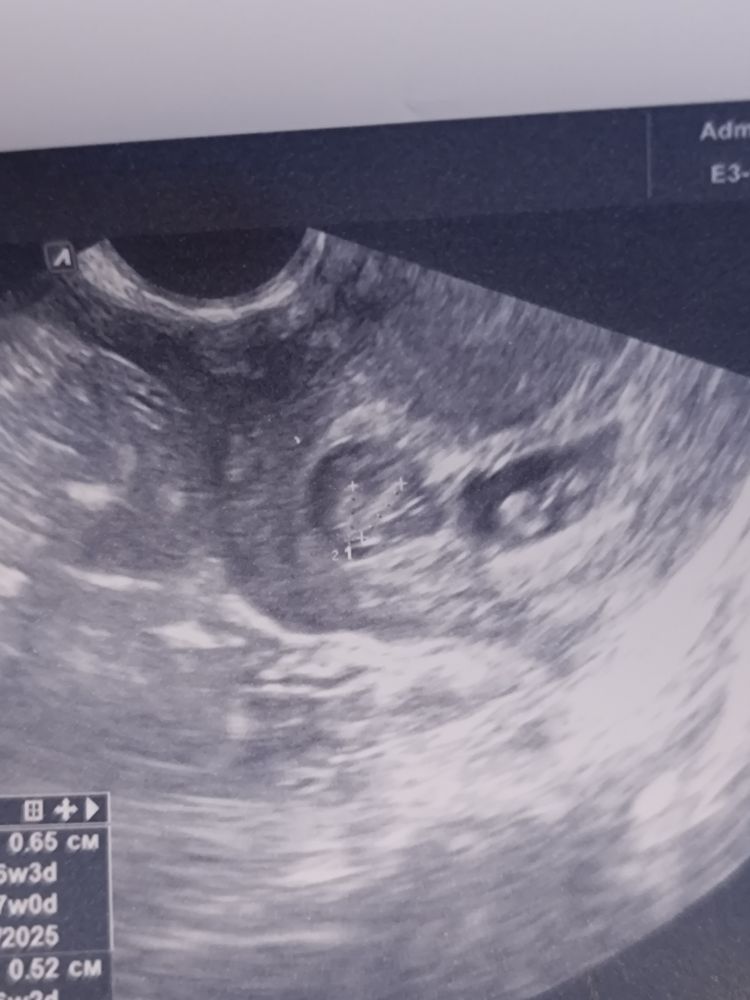

Тройня (2+1)